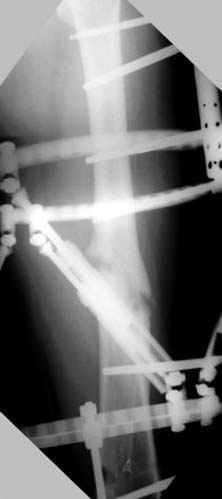

Несколько снимков из моей коллекции, чтобы разьяснить, почему мы до сих пор делаем различные варианты остеотомии.

На рисунке N1 предоперационный план лечения ложного сустава шейки бедра- линия ложного сустава, угол и направление введения импланта, клиновидная остеотомия в градусах и миллиметрах, второй снимок после коррекции, расчет, на сколько удлиняется конечность и размеры импланта;

N3 рисунок окончательный снимок, после операции моя рентгенограмма должен выглядеть примерно как эта картина. На N4 снимке клин перед удалением; N5 послеоперации 3 нед.; N6 окончательная рентгенограмма.

(доложен в Ст. Петербурге 2003 и в Москве 2004)

пластическая модель; и коррекция бедра аппаратом Илизарова.

Почему не замена гвоздя с рассверливанием, а аппарат?

Отправитель: Alexander Chelnokov 23 Ноябрь 2004, 21:29

хотя даже если бы и инфекция , то nail exchange с рассверливанием канала - вариант дебрайдмента) Я думаю, что последовательность развития событий:

Узкий к-м канал - тонкий гвоздь- усталостный перелом дистальных винтов - развитие нестабильности и как ее результат остеолиз вокруг гвоздя - деформация анатомической оси бедра. Похоже, что я понял почему аппарат, а не новый гвоздь:-)

ЕТ - Изначально костно-мозговой канал бедра был узкий, дальнейшее его рассверливание ещё больше скомпрометирует прочность бедра( латеральный кортекс дистального отломка уже истончен), приведет к дефекту наружной стенки - хотя это только мои догадки - хотелось бы знать мнение Джолдаса о выбранной тактике.